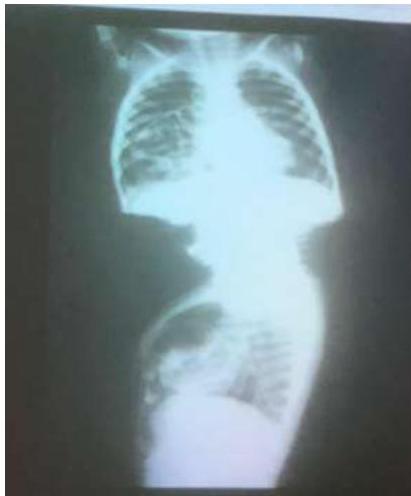

Diaphragmatic Hernia

- Anterior diaphragmatic hernia